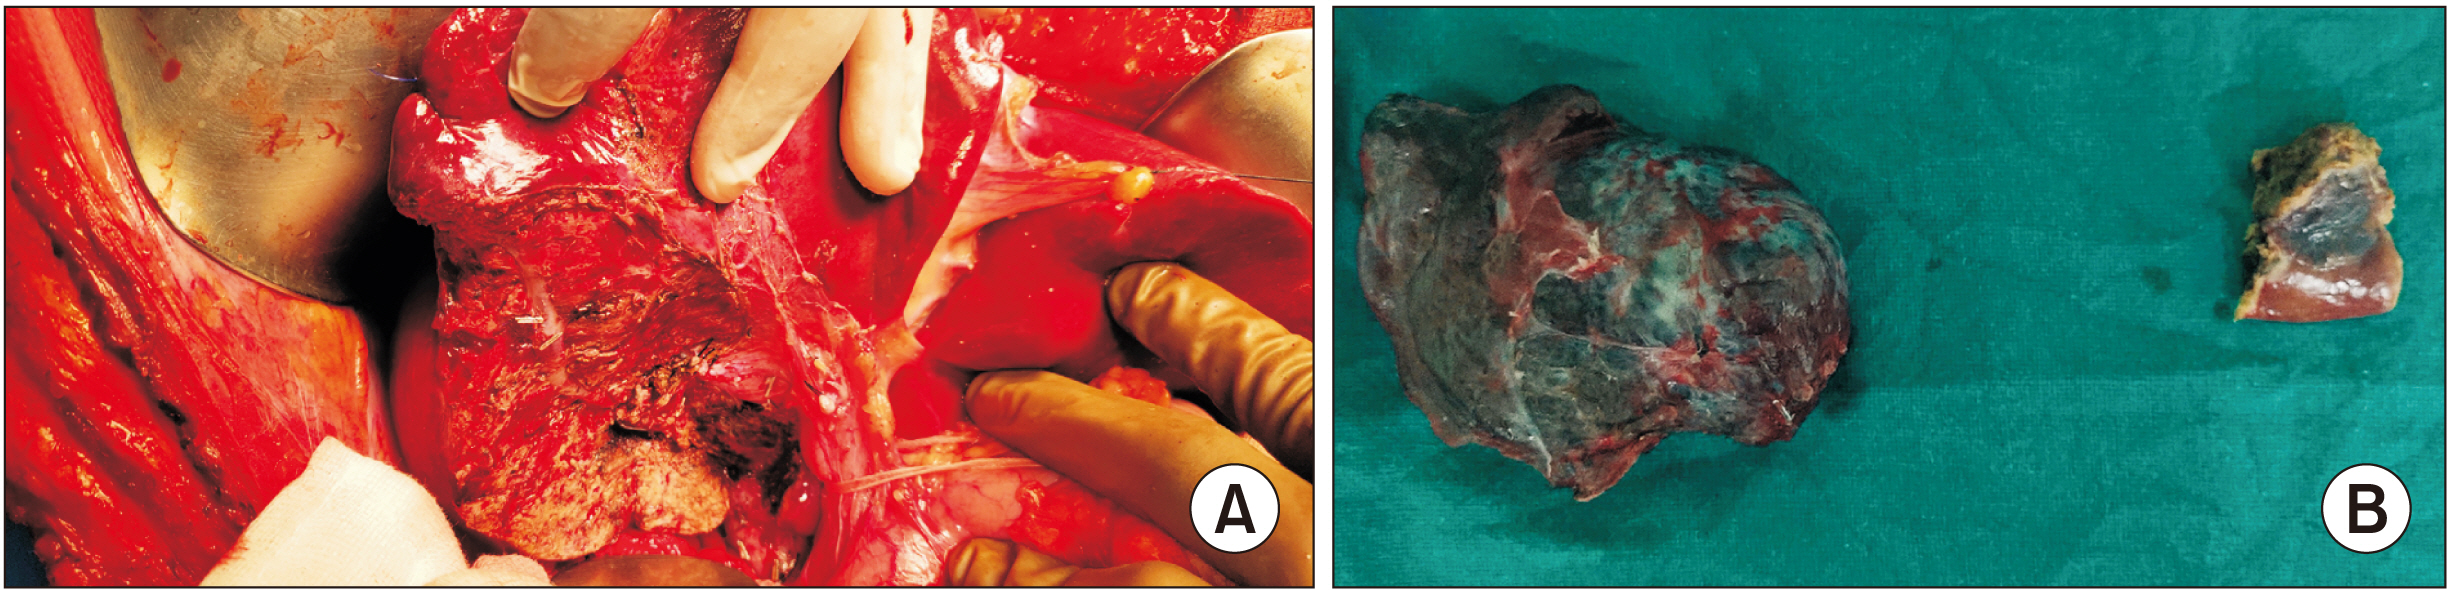

Figure